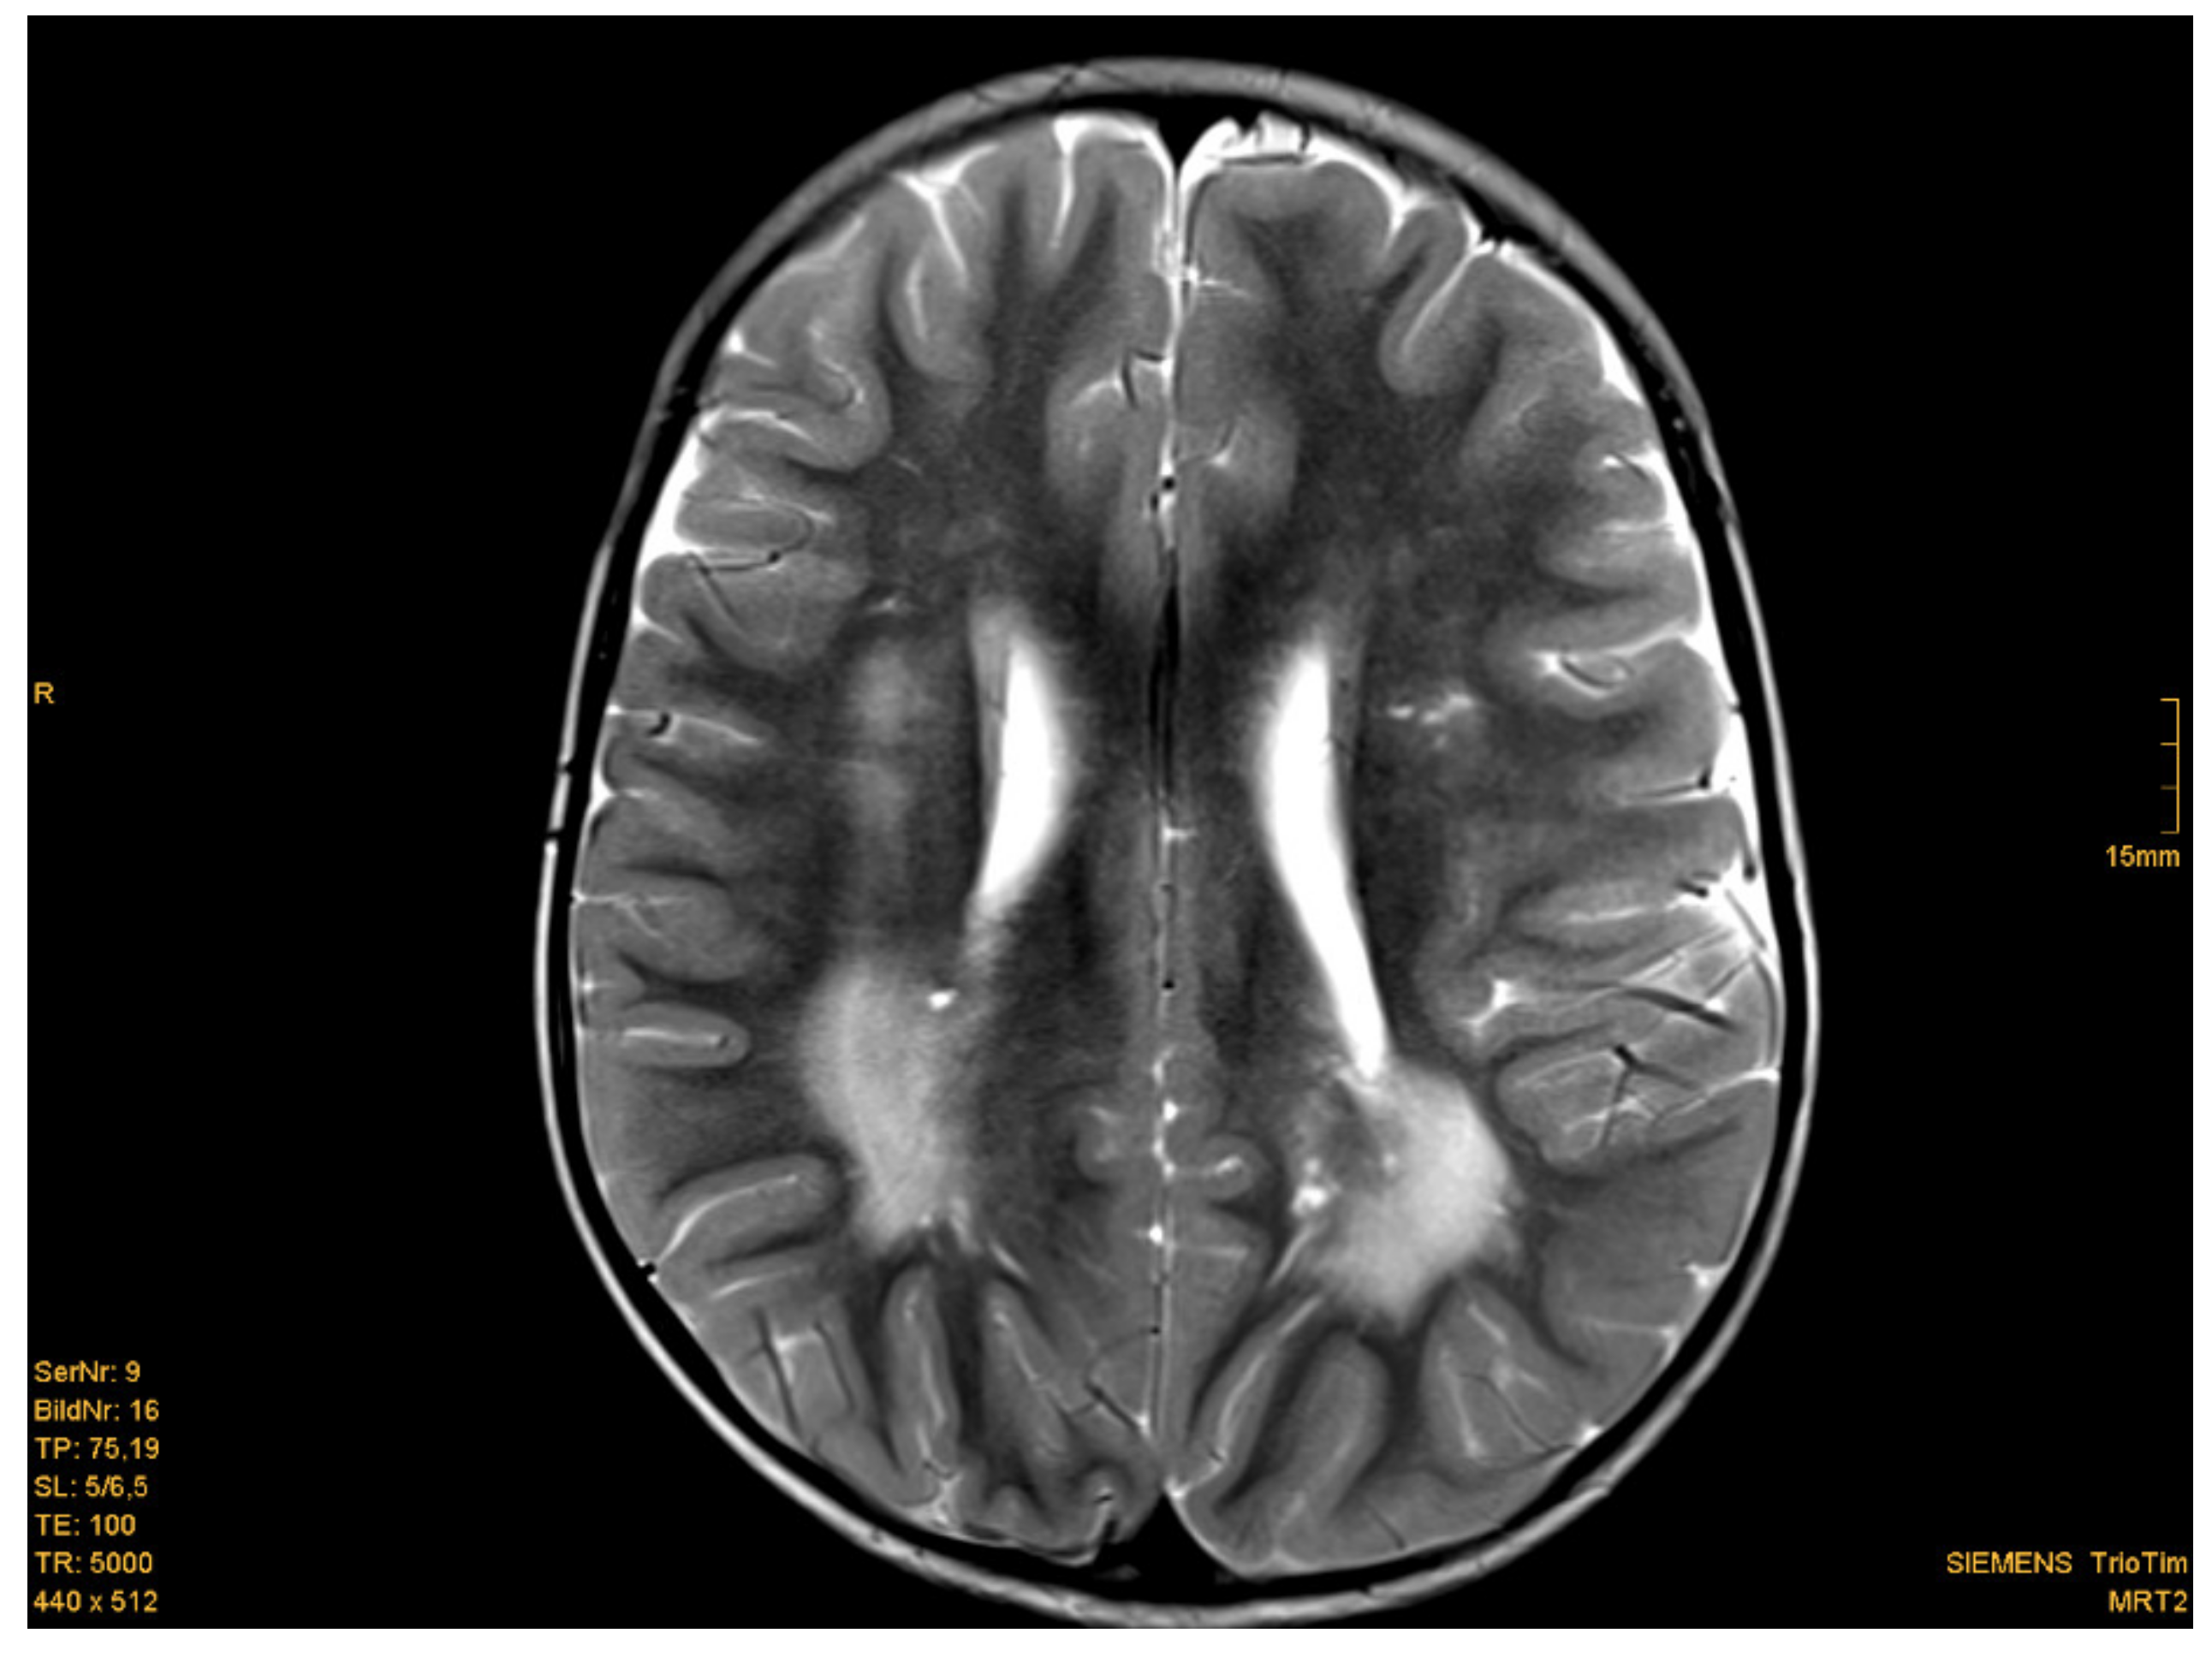

Eighteen of nineteen patients exhibited variations in cMRI. In 17 of 19 patients, we were able to re-analyze the MRI scans. In two cases, we only obtained medical reports, which were reported to be normal, even though enlarged perivascular spaces were described in one of these two patients. Medical reports of our patient cohort described enlarged perivascular spaces (EPVS), also known as Virchow–Robin Spaces (VRS), in six patients. However, when we re-analyzed the MRI pictures with special focus on EPVS, we found enlarged perivascular spaces in a total of eighteen patients (18/19). In some patients, these findings were quite evident (Figure 1b). Seven patients (7/17) presented with white matter abnormalities (Figure 2). Further pathologies included a cavernoma at the right side of the cerebellum, subependymal heterotopia at the top of the lateral cerebral ventricle, arachnoid cysts (in two), a Chiari malformation type I and a clinical diagnosis of pseudotumor cerebri with ventriculoperitoneal shunt in one patient (Table 1).

Figure 2.

Example of white matter abnormalities. Patient 6: 2 year-old boy, T2 weighted image. Posteriorly increased signal intensity of the white matter. [Courtesy Dr. Scharper, Radiology University Düsseldorf].